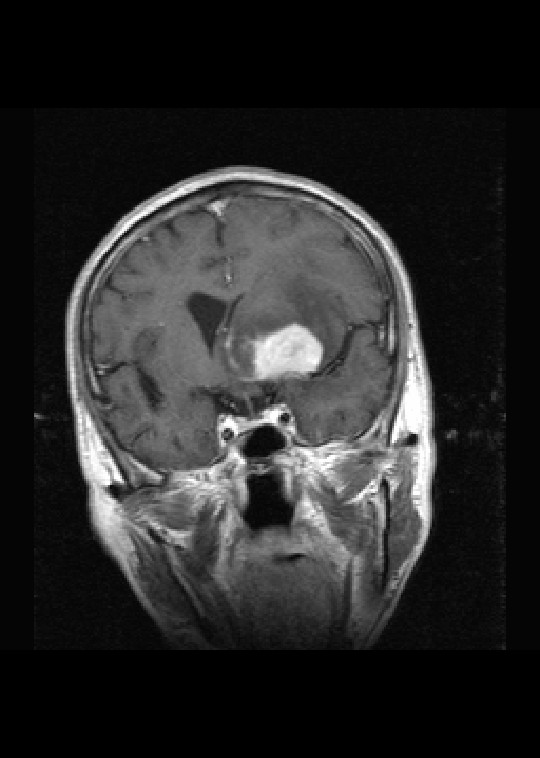

标题: MRI2527:脑部肿瘤,(病理结果:淋巴瘤)

(左额颞叶)非霍奇金淋巴瘤,b细胞性,弥漫性大b细胞型。免疫组化结果:cd45(lca) +,vimentin +,ck(ae1/ae3) -,ema -,cd3 -,cd20 +++,cd30 -,plap -,cd79a +,gfap -,alk -,s-100 -。

左侧基底节区病灶t1wi呈不均匀稍低信号,t2wi呈稍高信号,周围伴有水肿。增强扫描呈均匀团块样或者抱拳样明显强化,相邻的柔脑膜亦见线样强化。首先考虑淋巴瘤。可惜没有ct平扫,如果ct平扫病灶呈高密度,那么更支持pcnsl的诊断。

左侧基底节区长t1长t2异常团块状信号,增强呈明显均一强化,水肿明显,挤压侧脑室前脚,本人考虑为胶质瘤可能性大。

病理结果:(左额颞叶)非霍奇金淋巴瘤,b细胞性,弥漫性大b细胞型。免疫组化结果:cd45(lca) +,vimentin +,ck(ae1/ae3) -,ema -,cd3 -,cd20 +++,cd30 -,plap -,cd79a +,gfap -,alk -,s-100 -。

左侧基底节区病灶t1wi呈不均匀稍低信号,t2wi呈稍高信号,周围伴有水肿。增强扫描呈均匀团块样或者抱拳样明显强化,首先考虑淋巴瘤。